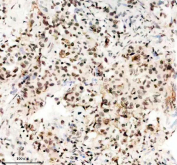

Immunohistochemical staining of FFPE human lung cancer tissue with TBX5 antibody, HRP-secondary and DAB substrate. HIER: boil tissue sections in pH8 EDTA for 20 min and allow to cool before testing.